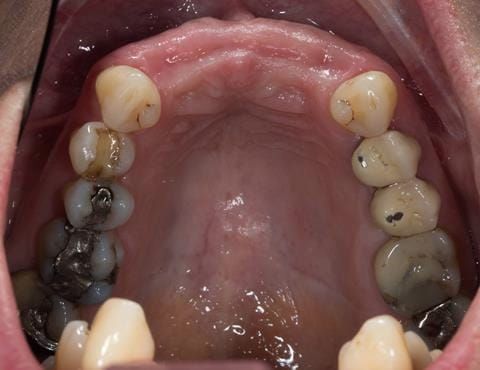

Provision of a maxillary cobalt chromium based partial denture/protective occlusal splint in a heavily restored dentition

- UR2 peri-radicular periodontitis with a peri-radicular area on the root apex. Retrograde amalgam filling from a previous apicectomy. No visible root canal or root canal filling. Large circumferential marginal gap between the crown and tooth. Large post and core present. Very little tooth structure remaining resulting in a fragile tooth with increased potential for fracture.

- UR1 peri-radicular periodontitis with a small peri-radicular area on the root apex with wide blunderbuss apex. Radio-opaque root canal filling present approximately 3 mm short of the radiographic apex. Large circumferential marginal gap between the crown and tooth. Large post and core present. Very little tooth structure remaining resulting in a fragile tooth with increased potential for fracture.

- UL1 peri-radicular periodontitis with a peri-radicular area on the root apex. Retrograde amalgam filling from a previous apicectomy. Visible root canal space with no sign of root canal filling. Large circumferential marginal gap between the crown and tooth. Large post and core present. Very little tooth structure remaining resulting in a fragile tooth with increased potential for fracture.

- UL2 peri-radicular periodontitis with a peri-radicular area on the root apex. No visible root canal or root canal filling. Large circumferential marginal gap between the crown and tooth. Large post and core present. Very little tooth structure remaining resulting in a fragile tooth with increased potential for fracture.

- High smile line showing gum above gingival zeniths of upper front teeth when smiling. Aesthetic failure of the upper four incisors with inflammation of the gingivae and mis-match of the gingival zenith levels.

- Other than the maxillary incisors the remaining dentition was in marginally better condition being moderately to heavily restored. Many will probably require replacement and restoration from time to time mainly from wear and tear owing to occlusal forces.